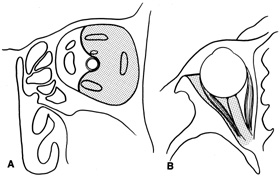

Lesions in the subperiosteal space that involve the orbital floor and roof of the maxillary sinus can be approached through an intraoral incision in the buccal sulcus above the upper canine incisors (Fig. 19). Dissection is carried through mucosa and soft tissue to the periosteum over the face of the maxilla. Dissection is carried superiorly in the subperiosteal plane to just below the inferior orbital rim. Care must be taken to identify the infraorbital nerve as it exits the foramen just below the rim. Osteotomies then are made in the face of the maxilla, and the underlying maxillary sinus is exposed. The sinus mucosa is excised and the roof of the sinus exposed in this fashion. Removal of the sinus roof (the orbital floor) allows exposure of the inferior periorbita. Care must be taken to avoid damage to the infraorbital nerve that runs within the bone of the floor. The inferior rectus muscle is encountered immediately above the periorbita, and it must be protected and retracted during deeper orbital dissection.

Fig. 19. Transantral inferior orbitotomy. The orbital floor (A) (roof of maxillary sinus) is exposed by an incision in the buccal sulcus and removal of the anterior face of the maxillary bone. The infraorbital nerve (B) traverses the floor of the orbit and exits on the face of the maxilla from the infraorbital foramen (C).

Indications

This approach often is used for orbital decompression in Graves' ophthalmopathy and cases of primary sinus pathology with secondary orbital involvement. It can be combined with a transconjunctival inferior orbitotomy approach to provide elevation and protection of orbital contents before removal of the orbital floor from below. It can be used to approach inferior peripheral lesions near the apex where an anterior-inferior orbital approach may not allow sufficiently deep access. However, better exposure may be afforded by a lateral orbitotomy in those cases.